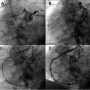

Employing a femoral approach, a 6 Fr AL 0.75 guide catheter (Cordis Corporation) was used initially to engage the left main artery. It was carefully lifted superior to the left main and non-selective catheter injection showed the RCA to originate superior to the left main (Figure 1A).

Figure 1. The AL 1 guide catheter was used, but given the anomalous origin, this could not coaxially align with the native vessel to provide adequate support for delivery of the stent. (A) Left coronary artery engaged, determining the origin of the right coronary artery (RCA) superior to the left main. The GuideLiner was anchored by having the AL 1 guide catheter close to the anomalous RCA, and placing the 0.14 wire down the RCA. (B) Fielder wire crossing lesions in right coronary artery. The 1.5 mm balloon was advanced into the RCA and the guideliner was railed over the 1.5 mm balloon and anchored into the proximal RCA providing coaxial support. (C) GuideLiner selectively coaxially engaging the ostium of the RCA until (D) improved flow following angiography (click thumbnail to view larger image).

There was thrombotic disease in the RCA, which likely led to the NSTEMI. Given the take-off of the vessel, the RCA could not be selectively engaged. After therapeutic doses of bivalirudin were given for anticoagulation, a 0.14 Fielder Wire (Asahi) was used to cross the lesions in the RCA (Figure 1B). Attempts were made to use the wire down the coronary as a rail to coaxially engage the RCA, but were unsuccessful. A 1.5 mm balloon was advanced down the vessel, over which a 6 Fr GuideLiner catheter was carefully used to selectively coaxially engage the ostium of the RCA (Figure 1C). Angiography revealed severe thrombotic disease in the RCA. Intracoronary IIb/IIIa inhibitors were given as well as verapamil and adenosine. Given the size of the GuideLiner catheter (5 Fr in 6 Fr guide), it was not possible to use a manual thrombectomy catheter. The lesions were stented with two Integrity bare-metal stents (Medtronic), 4.0 x 26 proximally and 3.5 x 30 mid. Finally, angiography revealed brisk flow and no residual and the patient’s chest pain had abated (Figure 1D). Intervention time and amount of contrast used were minimized by use of the GuideLiner catheter.